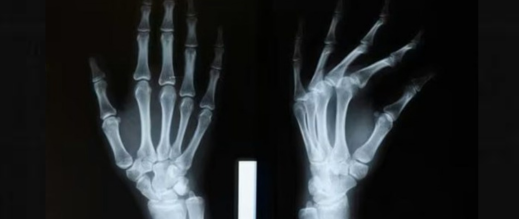

أعلن علماء صينيون عن تطوير غراء لاصق لعلاج كسور العظام، قادر على إصلاح الشظايا المكسورة والمهشمة في غضون ثلاث دقائق فقط.

وكشف فريق بحثي في مقاطعة تشجيانغ شرق الصين عن هذا الغراء، الذي أطلق عليه اسم “بون 02”، الأسبوع قبل الماضي، وفق تقرير صحيفة غلوبال تايمز الصينية.

وقال لين شيانفينغ، رئيس قسم جراحة العظام بمستشفى سير ران ران شو: إن فكرة تطوير الغراء جاءت من ملاحظة محار يتشبث بقوة بجسر تحت الماء، مشيراً إلى أن المادة اللاصقة قادرة على إصلاح الكسور خلال دقيقتين إلى ثلاث دقائق، حتى في الحالات التي تكون فيها الإصابة غنية بالدم.

ويعد هذا الابتكار خطوة نوعية في علاج كسور العظام، لما يوفره من تثبيت سريع وفعال يقلل الحاجة إلى العمليات الجراحية التقليدية.